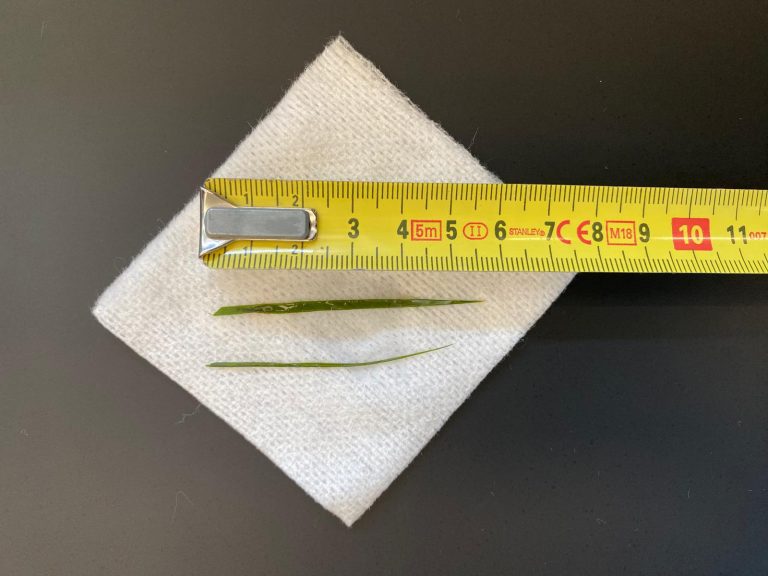

Hierna hebben we een urinekatheter ingebracht die na 4 cm vastliep op een harde structuur. Op de röntgenfoto is er bij de pijl een blaassteen te zien die vastgelopen is in het penisbotje.